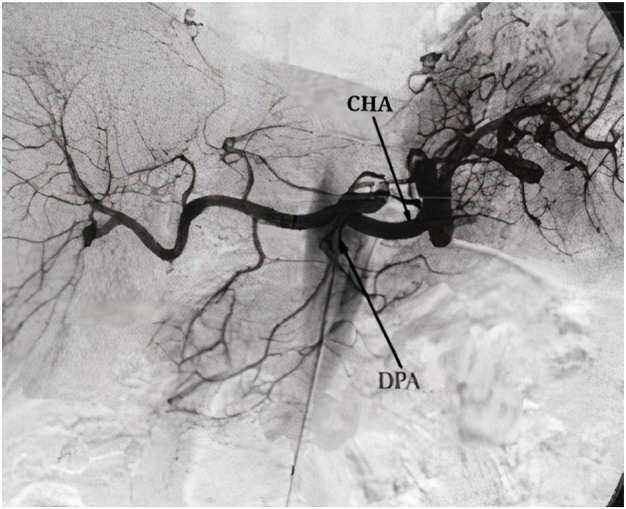

Results: The study identified three major types of arterial variations. The dorsal pancreatic artery (DPA) was observed to arise from the splenic artery (SPA), common hepatic artery (CHA), and superior mesenteric artery (SMA). The prevalence of arterial variations in the observed population (single-center study) in this research was found to be different from that reported in previous studies conducted on other populations. Specifically, the study found a higher incidence of DPA variations arising from the SPA (in 73% of the participants). The origin from the SMA was seen in 24% of patients and from the CHA in 3% of patients. The length, width, and other characteristics of the pancreatic arteries were also carefully documented. The study also found no significant correlation between arterial variations and the presence of diabetes mellitus or MS. One of the variations was found to display minor constriction but was not significant enough to be considered pathological.